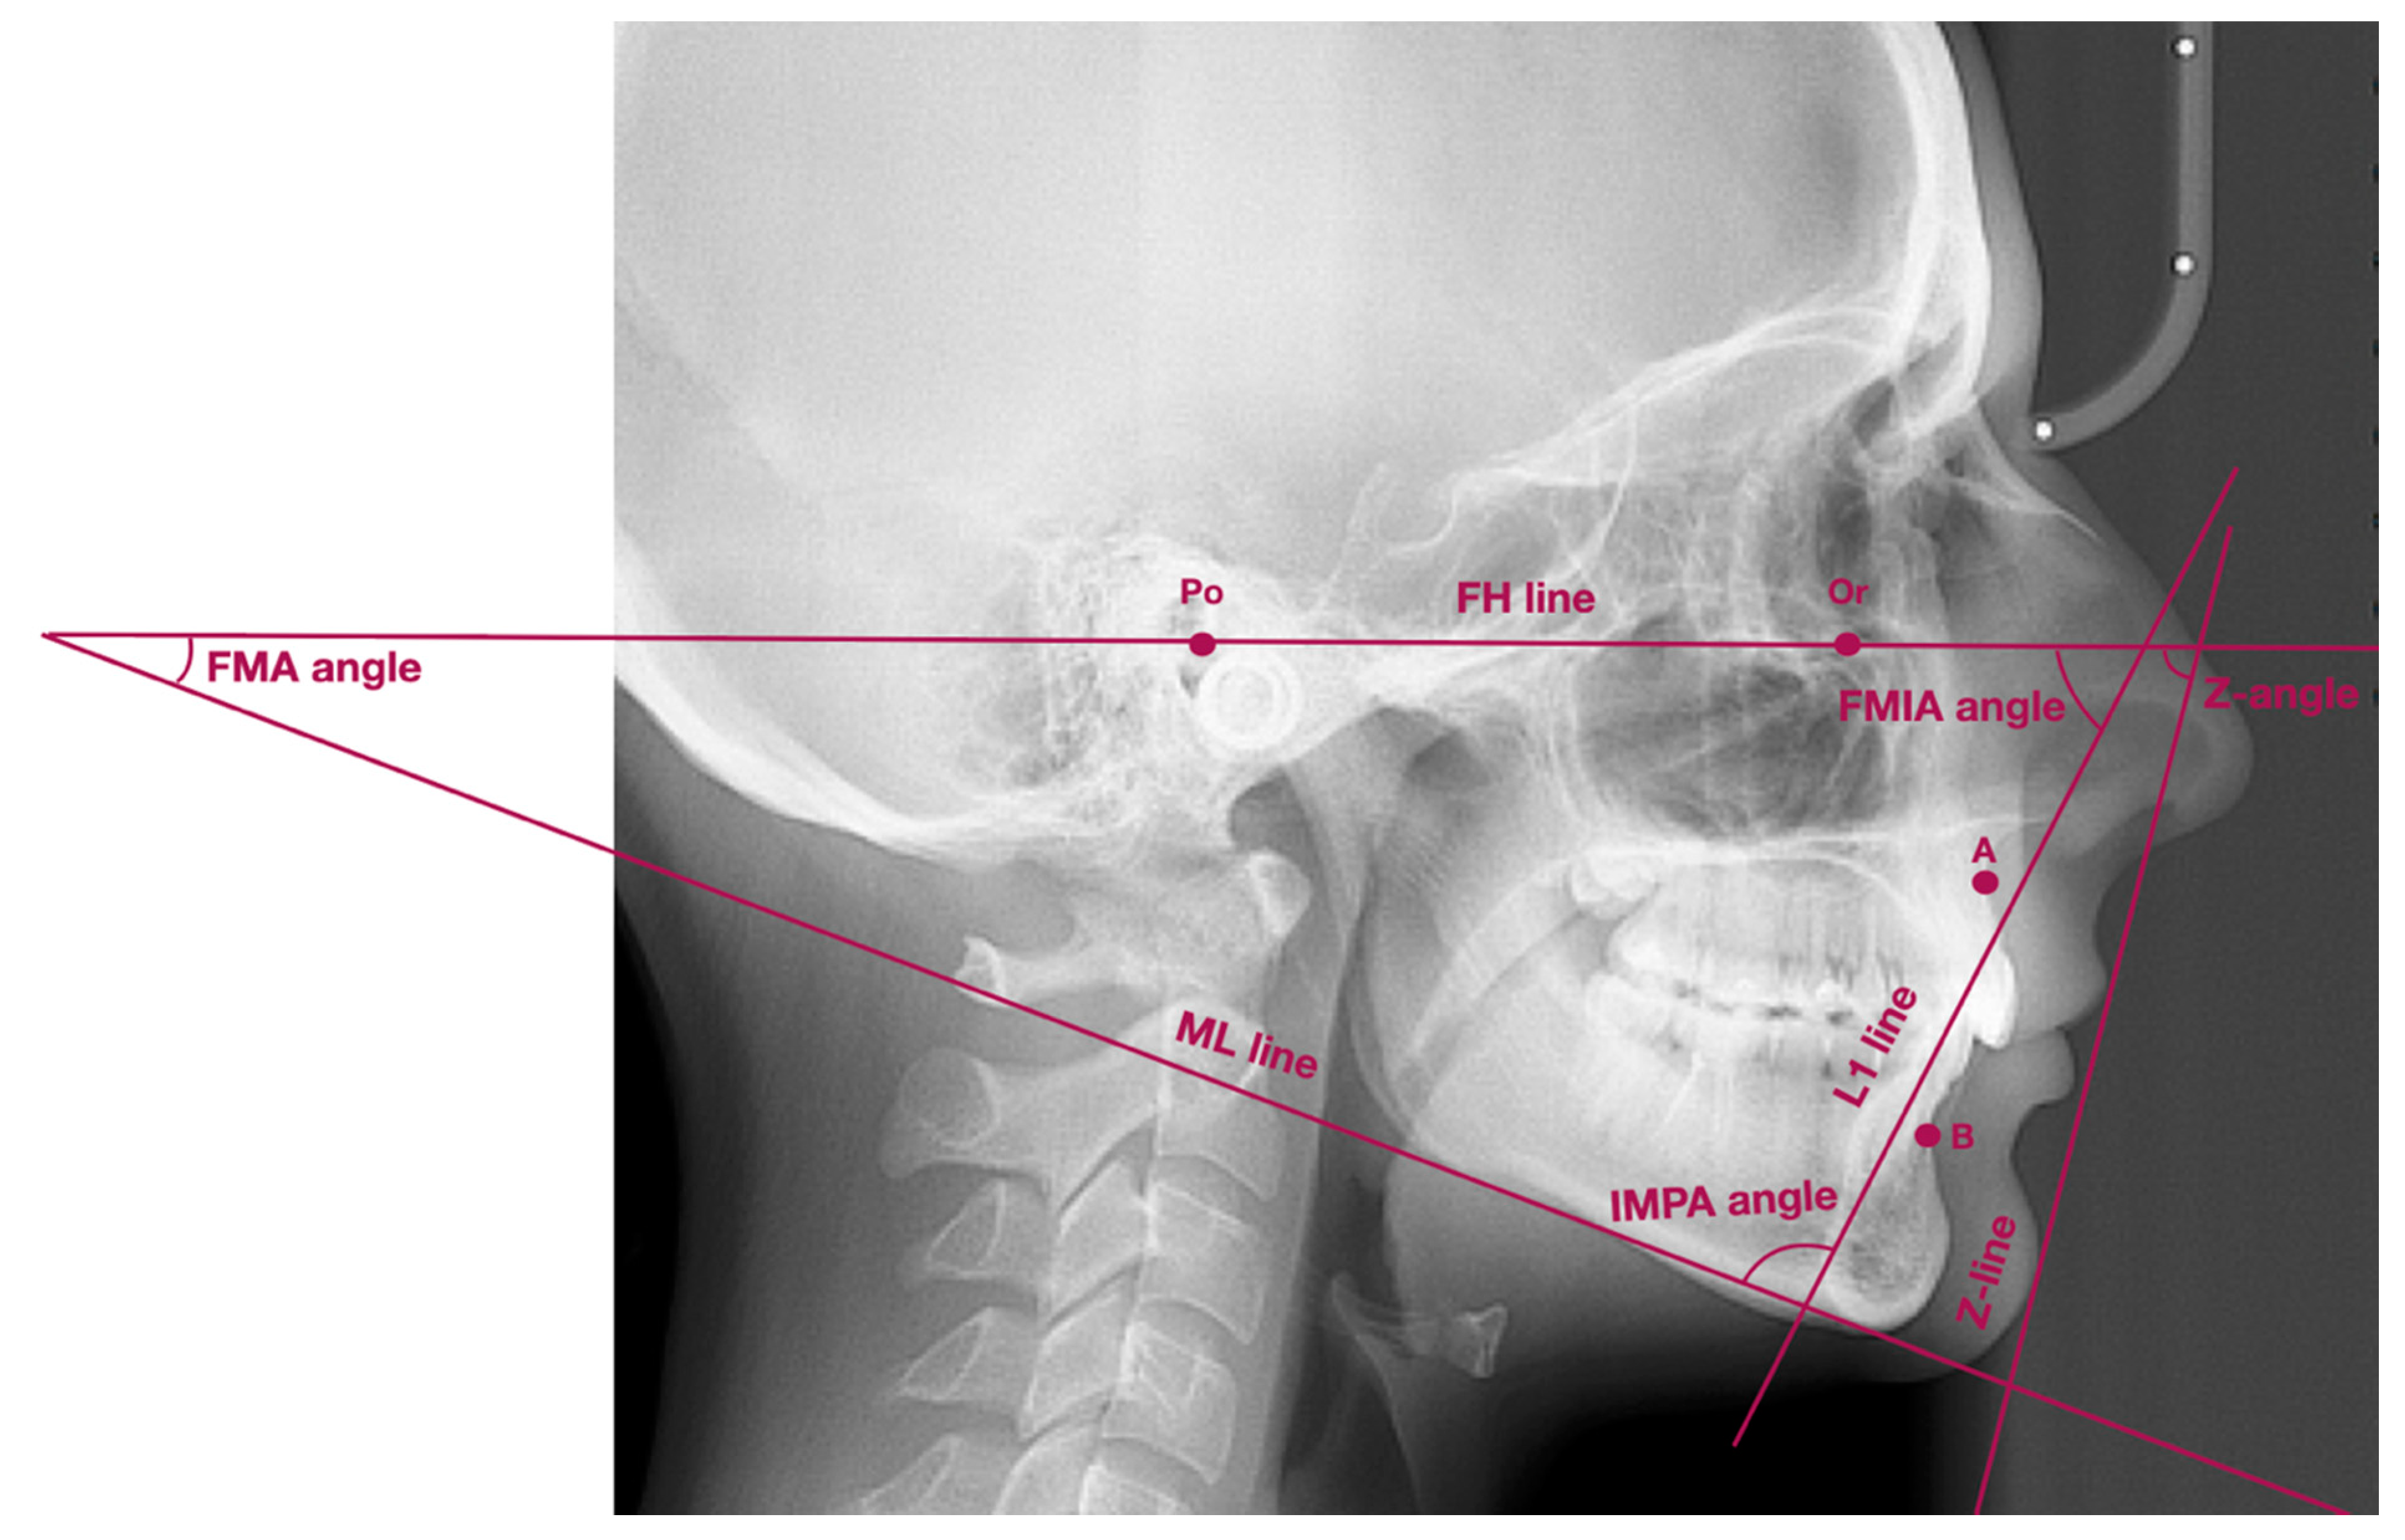

| Points/Lines/Angles | Description of Points/Lines/Angles |

|---|---|

| Point Po | Porion—the most superior part of external acoustic opening |

| Point Or | Orbitale—the most inferior point localized in the lower margin of the orbit |

| Point A | Subspinale—the deepest point localized in the anterior outline of the maxilla, below the anterior nasal spine |

| Point B | Supramentale—the deepest point localized in the anterior outline of the mandible, above the pogonion |

| Wits | AO-BO—distance between the perpendicular projection of points A and B onto the functional occlusal plane |

| ML line | Mandibular line—line between gnathion and the lowest point localized in the masseteric tuberosity (also known as GoGn line) |

| FH line | Frankfort horizontal line—line between points: porion and orbitale |

| L1 line | Long axis of lower incisor—line which connects the incisal edge with the radiological apex of lower incisor |

| Z-line | Z-line (the profile line)—line which connects the most prominent point on soft-tissue chin with the most prominent point on either upper or lower lip, depending on which lip was more protruded |

| FMA angle | Angle between FH line and ML line |

| FMIA angle | Angle between FH line and long axis of lower incisor |

| IMPA angle | Angle between long axis of lower incisor and ML line |

| Z-angle | Angle between Z-line and FH line |